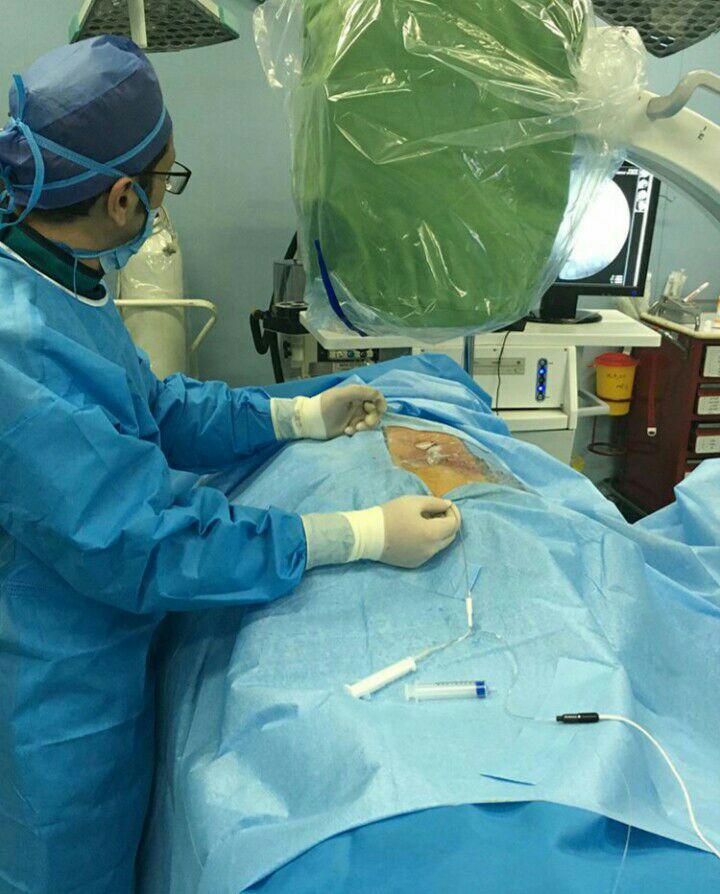

-لیزر(جراحی بسته) دیسک کمری

استفاده از روشهایی مانند تزریقات تخصصی (مانند اپیدورال، بلوک عصبی)، طب سوزنی، فیزیوتراپی، تحریک الکتریکی عصب و روشهای کم تهاجمی جراحی.